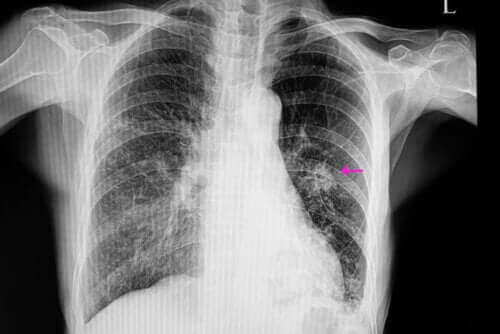

Σε τέτοιες περιπτώσεις, οι θρόμβοι έχουν μια ακανόνιστη εμφάνιση με όρια που προσδιορίζονται δύσκολα. Αυτοί είναι ορατοί σε μια ακτινογραφία. Επίσης, συνήθως είναι μικρότεροι από τους καλοήθεις. Επιπλέον, αποτελούν τμήμα των παραγόντων επικινδυνότητας όπως:

Μόλις γίνουν τα παραπάνω, ο γιατρός θα πρέπει να εκτελέσει ορισμένες εξετάσεις απεικόνισης για να εντοπίσει τον θρόμβο. Επιπλέον, οι εικόνες θα του επιτρέψουν να παρατηρήσει ορισμένα χαρακτηριστικά όπως το σχήμα και το μέγεθος. Αυτό επειδή είναι σημαντικά στοιχεία για τη διαφοροποίηση ενός καλοήθη θρόμβου από έναν κακοήθη.

Οι πιο συχνοί τρόποι διάγνωσης είναι μια ακτινογραφία θώρακα και αξονικές τομογραφίες. Για να φανεί η ακριβής αιτία ενός θρόμβου στον πνεύμονα, οι γιατροί καταφεύγουν σε βιοψίες κάποιες φορές, καθώς αυτές τους επιτρέπουν να αναλύσουν τον ιστό.